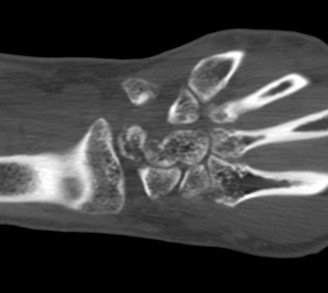

¼Õ¸ñ ÀåÃø Á¾´Ü¸é°Ë»ç¿¡¼­ ¿ù»ó°ñ °ñ±ØÀÌ °üÂûµÊ(»çÁø 2).